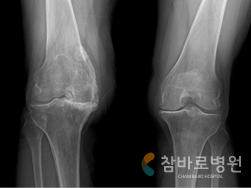

퇴행성 관절염 사진

연골이 심하게 마모된 퇴행성 관절